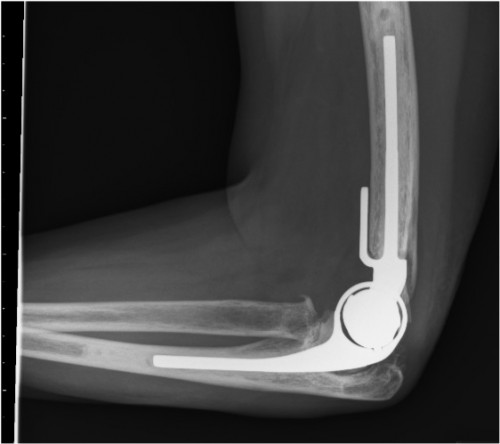

Me përvojën e tij 30-vjeçare në fushën e mjekësisë dhe 23-vjeçare në fushën e kirurgjisë ortopedike, ai është i përqendruar në artroplastikën totale të artikulacioneve (koksofemoral, gjurit, kyçit të këmbës, shpatullës, bërrylit, kyçit të dorës dhe artikulacioneve të vogla). Dhe ka një numër të madh suksesesh në rastet që kanë kryer protezim total të artikulacionit koksofemoral displazik dhe të dislokuar.

- protezimi i bërrylit